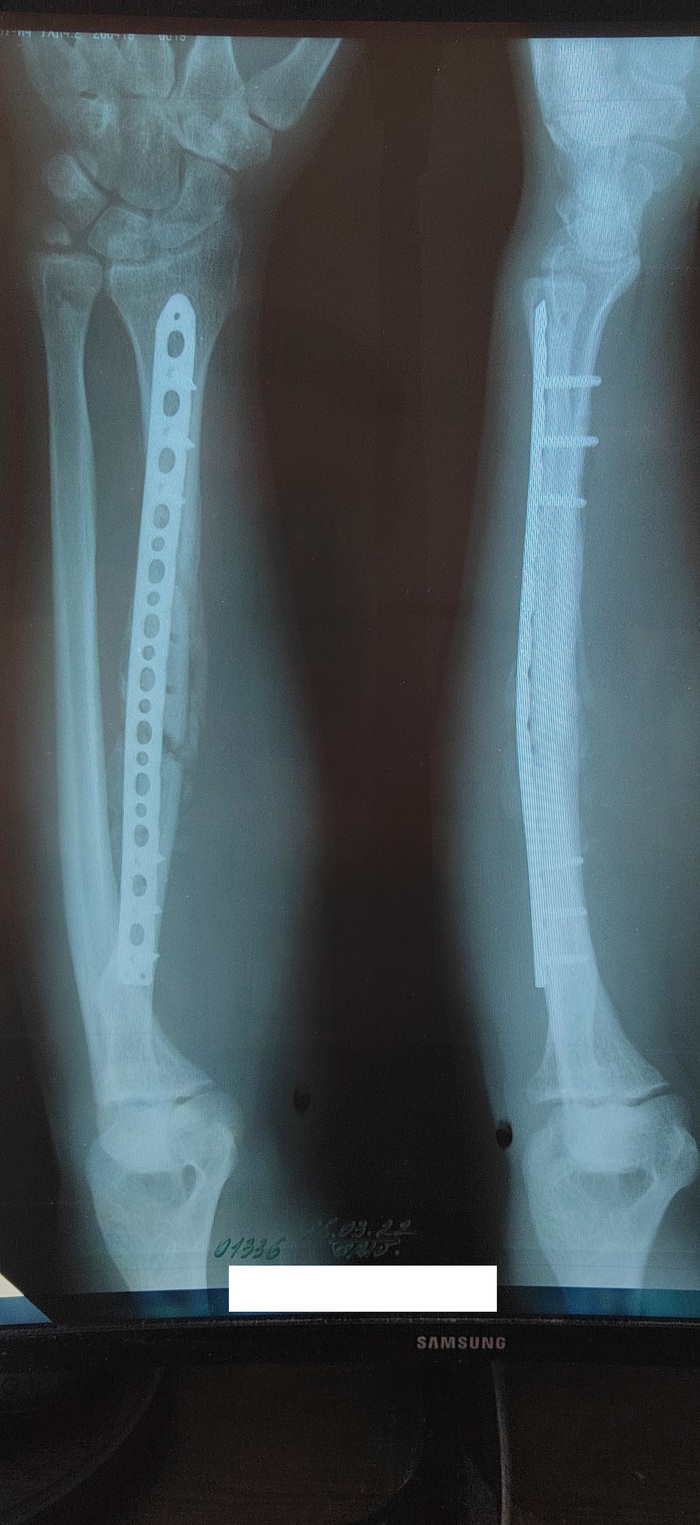

Доброго времени суток, уважаемые Пикабушники. Более 8 лет я сохранял молчание, но со мной произошла история, о которой я бы хотел вам рассказать. Начну с начала. В июле 2021 года со мной произошёл несчастный случай на стадионе, результатом которого стал переломовывих Голиацции правого предплечья. Был экстренно госпитализирован. Первая операция - Аппарат Илизарова. Вытяжение. Вторая операция - Открытая репозиция МОС лучевой кости пластиной. Дистального сочленения - спицей. И всё вроде бы хорошо, но на этом не закончилось.

Пришла зима, а с ней и снегопады. Пошёл я чистить снег и упал. Прямо на пластину в руке. Результатом стал повторный множественный перелом правого предплечья. Следом за ним третья операция по рефрактуре правой лучевой кости.

И новая металлоконструкция